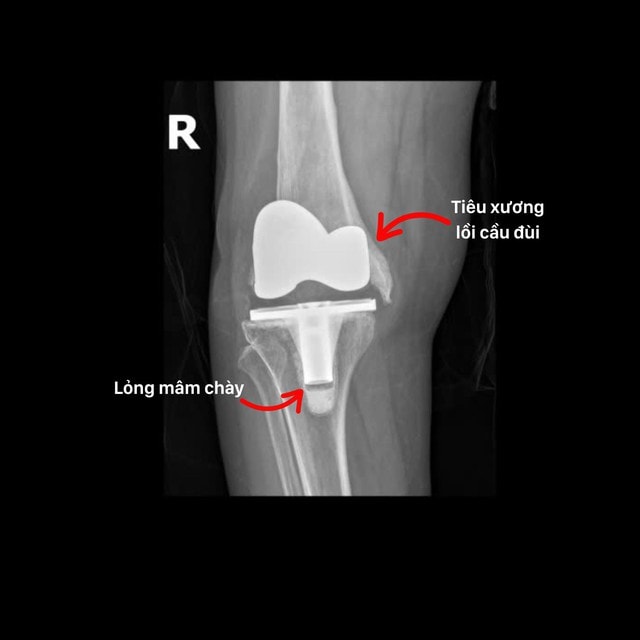

Mới đây, ThS.BS Trương Xuân Quang cùng ê-kíp BVĐK Hồng Ngọc đã thực hiện thành công ca thay lại khớp gối phức tạp cho bệnh nhân N.T.T (72 tuổi - Hưng Yên). Cách đây 3 năm, bệnh nhân từng thay khớp gối tại bệnh viện địa phương nhưng do kích ứng của cơ thể nên phần xương bị tiêu gần hết khiến khớp nhân tạo lỏng lẻo và lệch khỏi cấu trúc giải phẫu gây sưng đau, biến dạng khớp, mất vận động.

"Đây là trường hợp hiếm gặp bởi bệnh nhân bị mất hoàn toàn phần lồi cầu xương đùi, không còn điểm tựa để cố định khớp gối mới. Phẫu thuật viên phải thay lại khớp gối đồng thời tái tạo lại lồi cầu xương đùi (đầu dưới xương đùi) để tạo độ vững và giúp khớp vận động linh hoạt. THS.BS Trương Xuân Quang cho biết.

Chia sẻ về quá trình phẫu thuật, BS Quang nhấn mạnh: Quá trình phẫu thuật chúng tôi đã tháo toàn bộ khớp nhân tạo cũ, tái tạo lồi cầu bằng xi măng sinh học và cố định tạm bằng kim Kirschner. Khớp gối nhân tạo mới được chọn là loại chuôi dài, bám sâu vào ống tủy, giúp khớp ổn định và cải thiện biên độ vận động. Đồng thời tối ưu chi phí so với ghép xương hoặc sử dụng bộ khớp lồi cầu nhân tạo chuyên biệt".